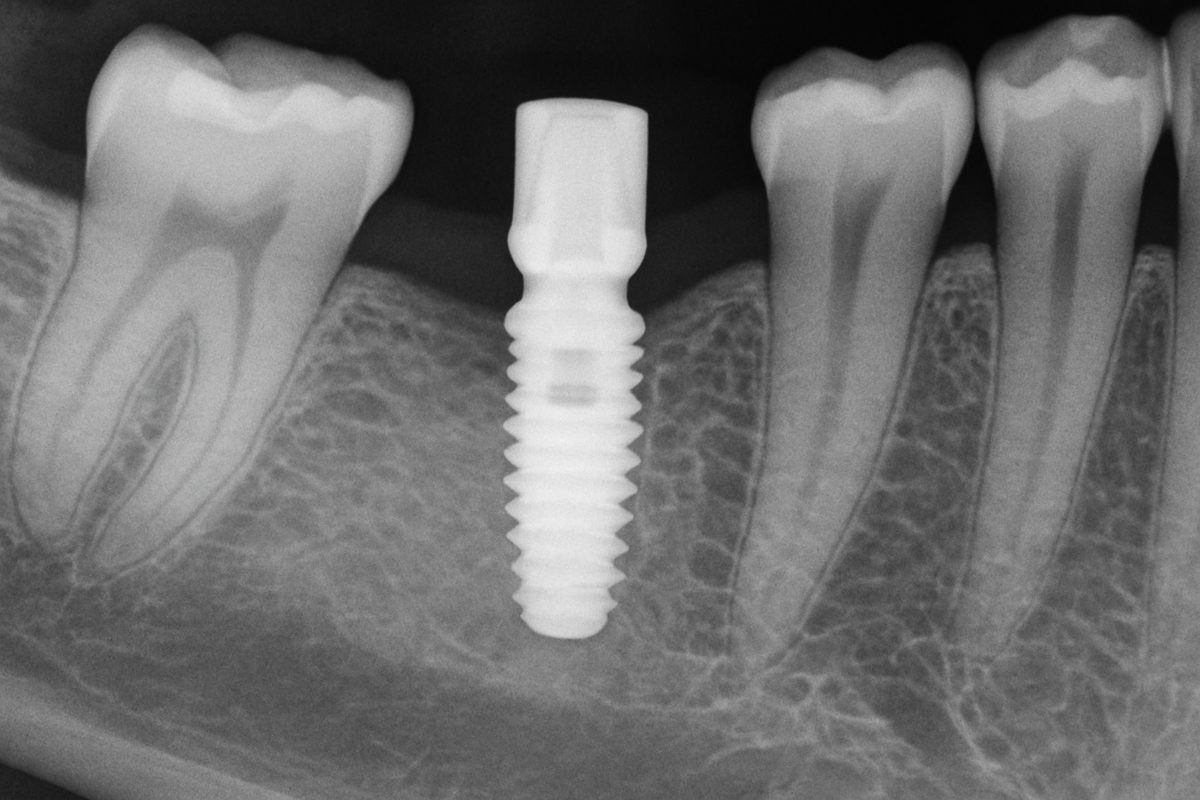

Denture implants use titanium posts placed in the jaw to anchor a denture. There are two main options: implant-retained overdentures that snap onto 2–4 implants but can be removed for cleaning, and implant-supported fixed dentures that attach to 4–8 implants and stay in place like natural teeth. Both types are more stable than traditional removable dentures because they stop the denture from shifting and help preserve jawbone by transmitting chewing forces to the bone.

Good candidates usually have healthy gums and enough jawbone to support implants. If bone has resorbed after tooth loss, bone grafting or sinus lifts can rebuild volume so implants can be placed. Your implant dentist will use X-rays or a CBCT scan to evaluate bone density and plan treatment.

Your dentist will perform an exam, take digital X-rays and often a CBCT scan to map bone and nerves. They’ll review medical history, take impressions or digital scans, and discuss options and costs. Planning determines implant number, placement, and whether grafting is needed.

Implant placement is an outpatient surgery. Local anesthesia and sedation options are available. The dentist places the titanium posts into the jaw and covers them to heal, or sometimes attaches an immediate temporary prosthesis if primary stability allows. Healing (osseointegration) can take 3–6 months before final teeth are attached.